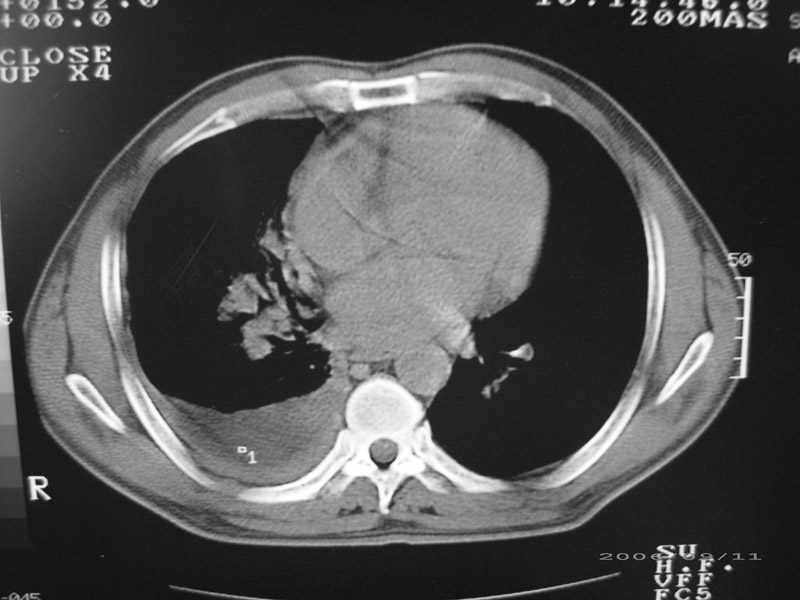

以下是引用守望可可西里在2006-9-11 15:29:00的发言:[br][br] ct平扫表现:右侧胸膜腔缩小,积液,胸膜增厚且不均匀、不规则,以纵隔胸膜增厚为主,边缘呈锯齿状,并见附壁内突之结节状肿块影。右肺含气量减少,纹理聚集,右肺门中下部见数个肿大的淋巴结。纵隔无移位,内未见明显肿大淋巴结,双侧主支气管以及各叶、段支气管比较通畅。。[br] 考虑:右侧胸膜恶性间皮瘤,伴肺门淋巴结转移。